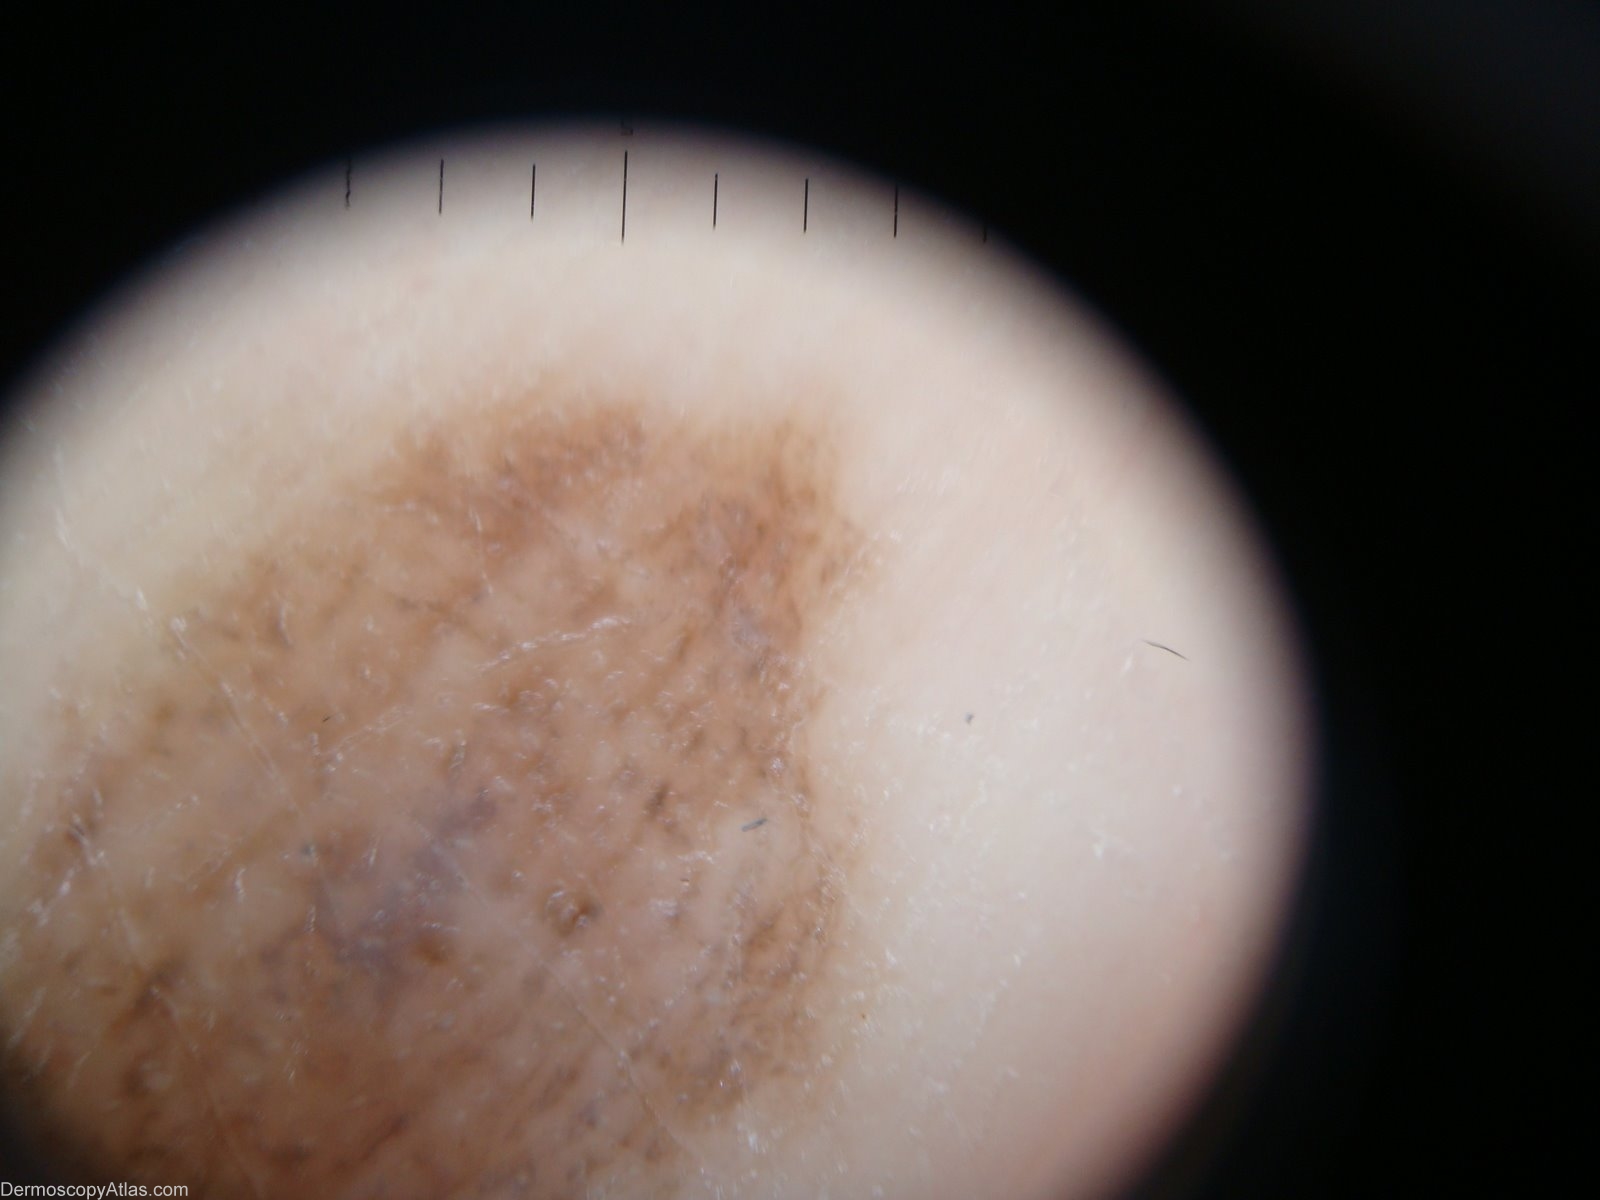

Image Number #3094 (Acral congenital naevus)

Site: Foot,sole

Diagnosis: Acral congenital naevus

Description: Parallel furrow pattern and blue-gray central area

History: This 45 years old woman have this lesion since birth. Dermoscopic description: Parallel furrow pattern (always the PFP must be estimate on the lateral borders) and blue-gray central area which is a sign of congenital.